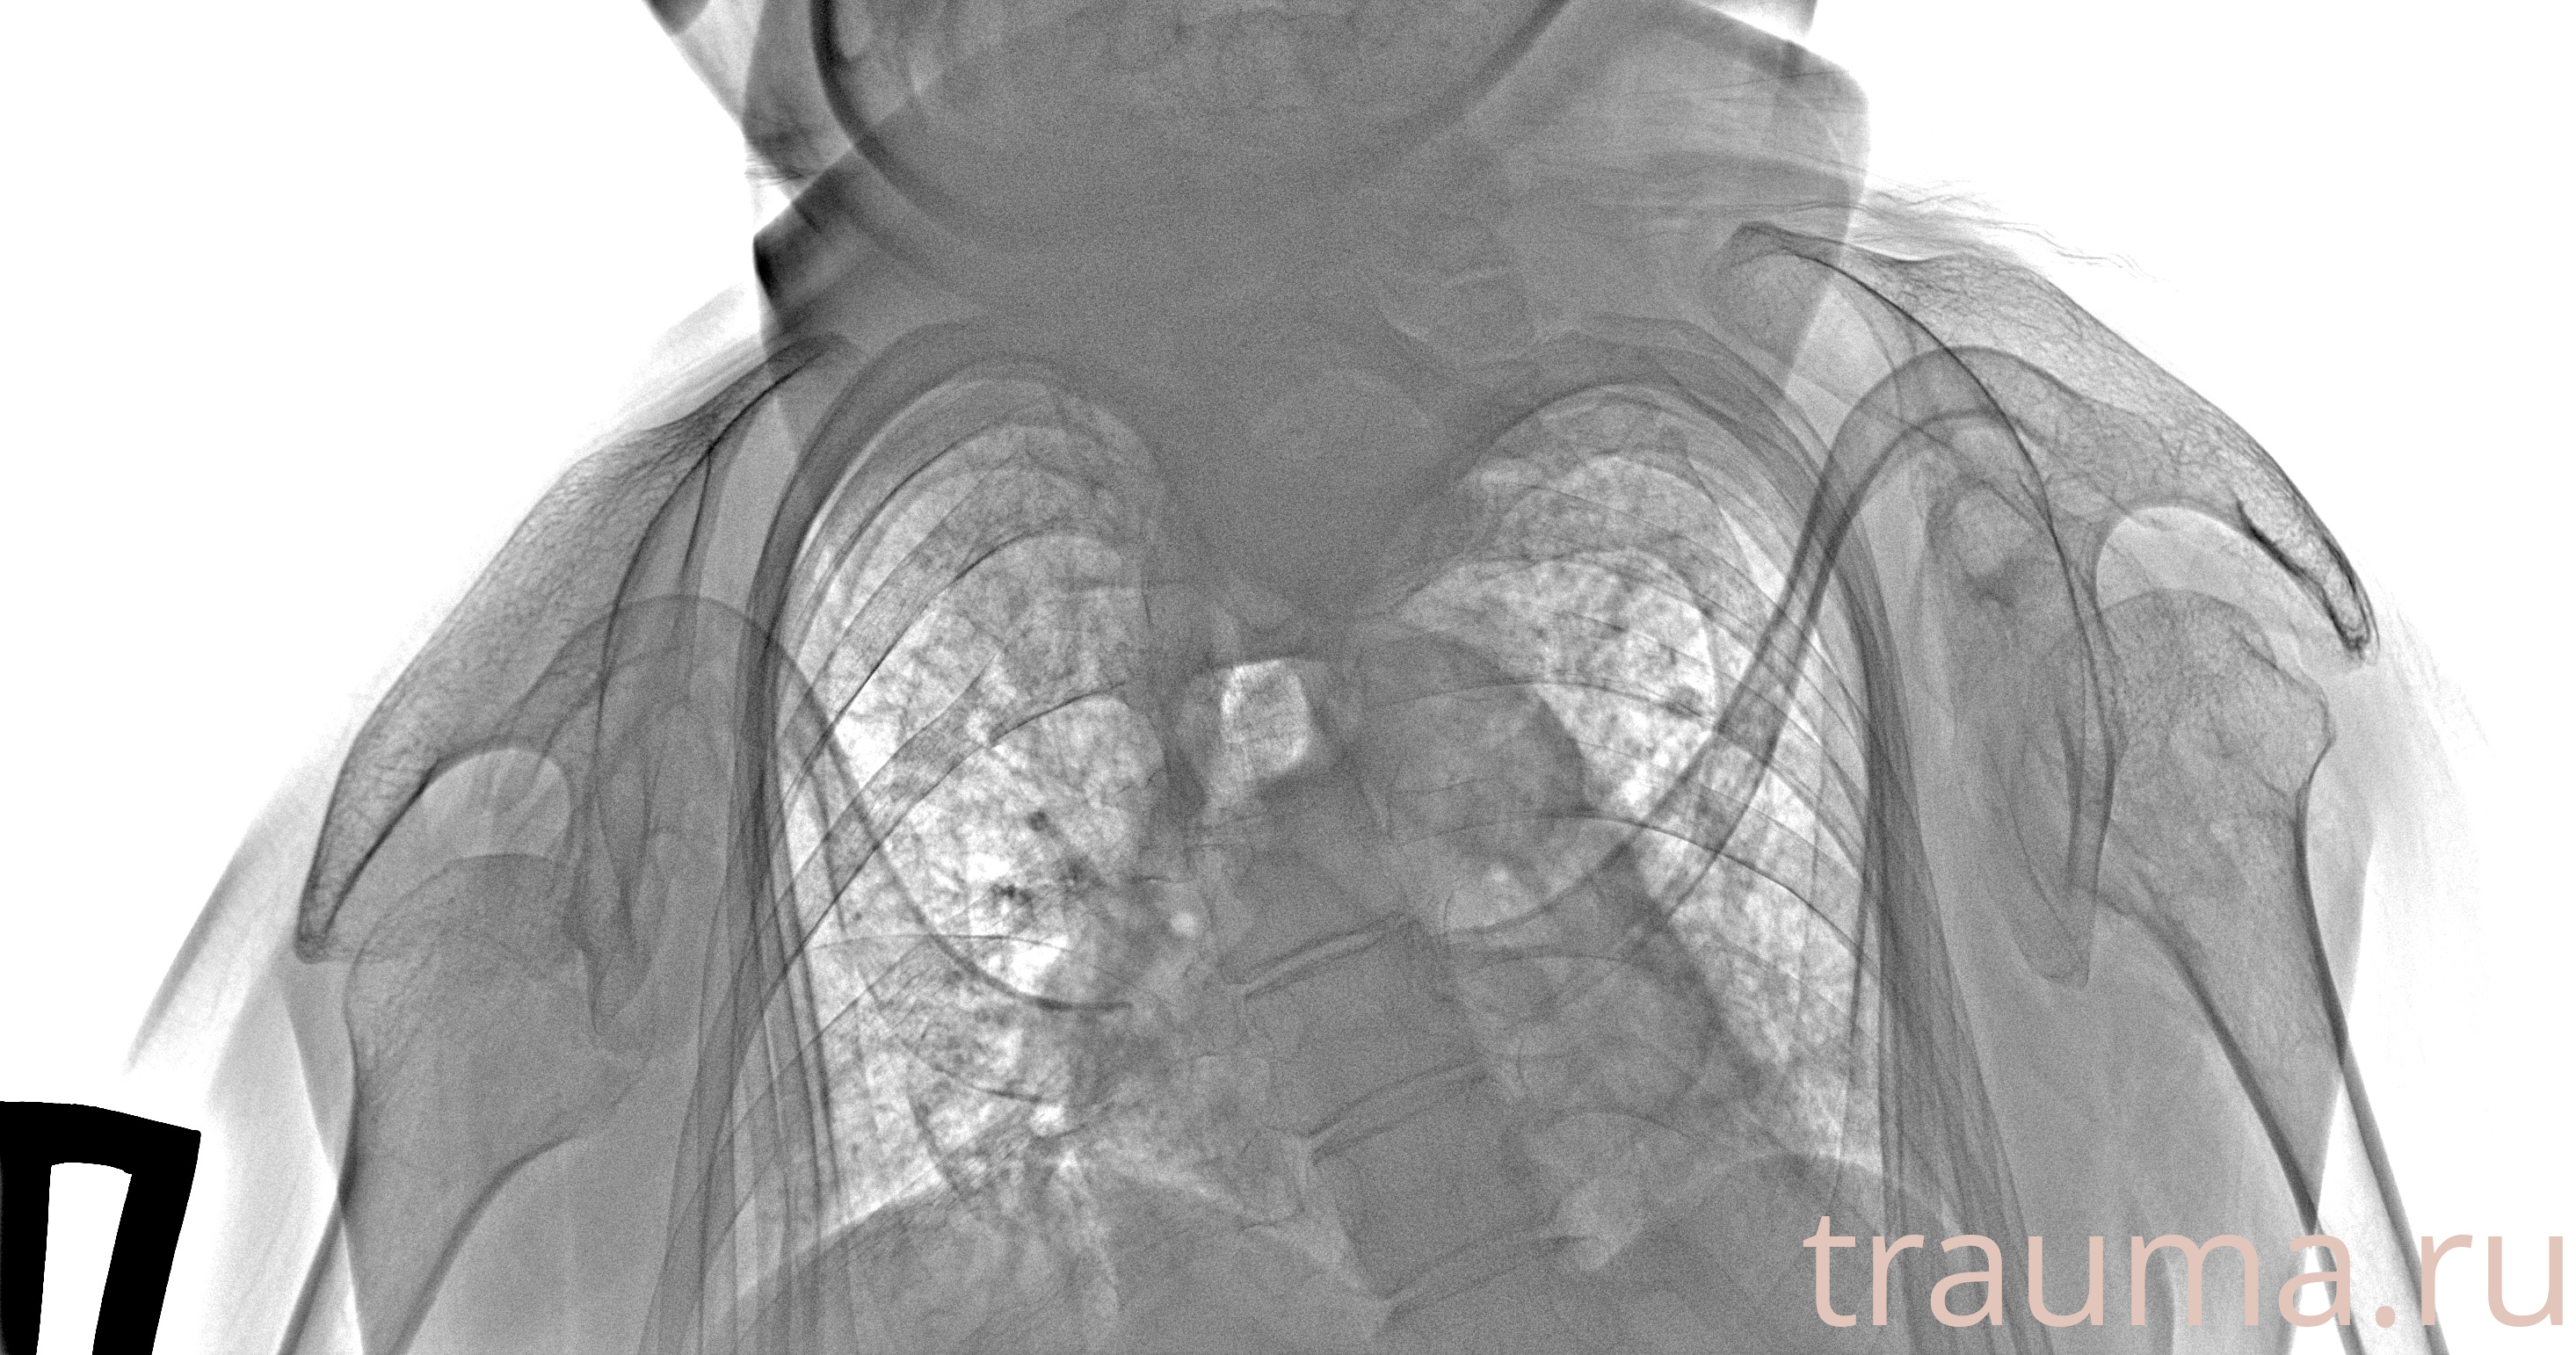

Рентген на дому: по вашему адресу приезжает врач-рентгенолог, травматолог-ортопед с мобильным рентгеновским аппаратом, проводит диагностику травмы или заболевания, делает необходимые рентгенограммы, дает рекомендации по дальнейшему лечению. Получить качественные снимки в домашних условиях возможно благодаря уникальной методике, разработанной МосРентген Центром для института  Склифосовского